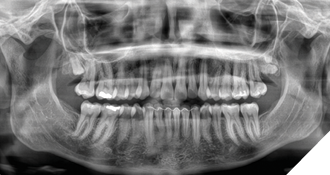

The patient was seen again 1 year following for radiologic reassessment and remained asymptomatic. The maxillary third molars were noted to have descended relative to the primary assessment, with increased mineralization of the maxillary supernumerary tooth (Fig. 2).

Fig. 2